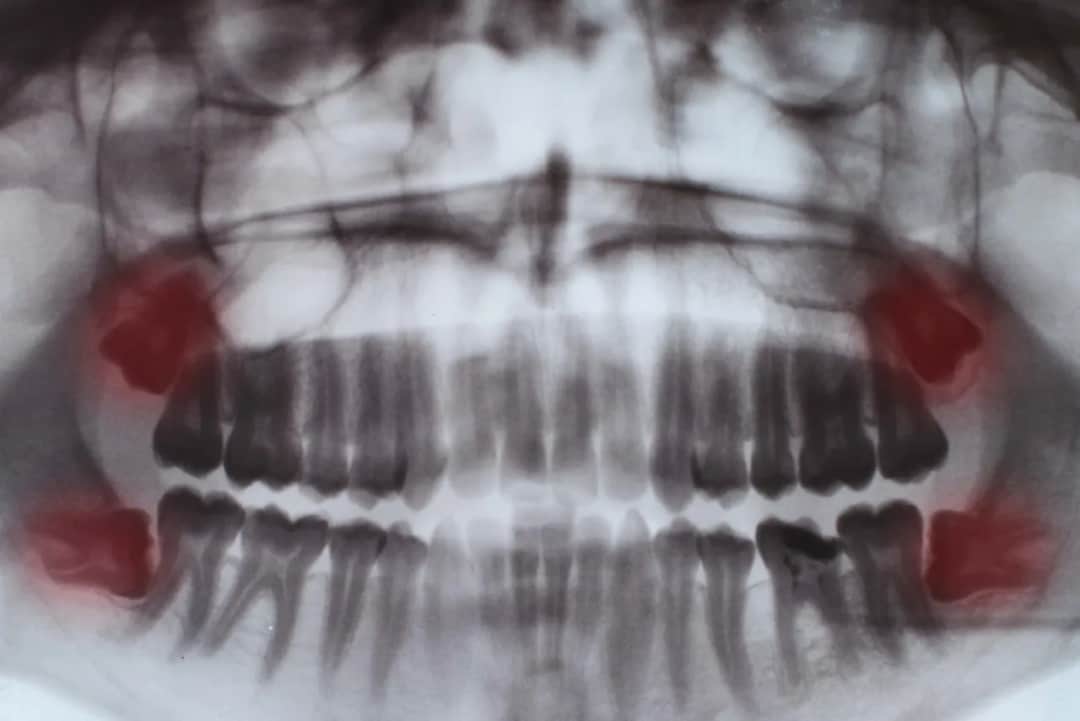

Dowiedz się, kiedy rosną zęby mądrości (17-25 lat), jakie objawy towarzyszą ich wyrzynaniu i jak radzić sobie z bólem. Sprawdź, kiedy wizyta u dentysty jest konieczna.